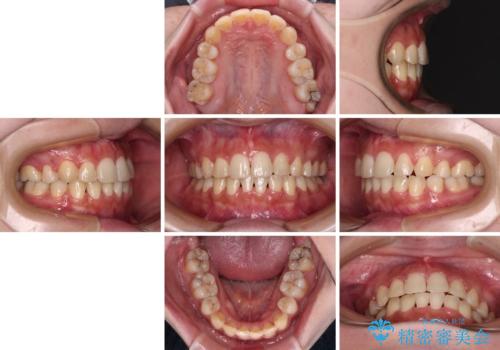

- 八重歯やデコボコをインビザラインで治療したいとのことで来院された患者様です。

インビザライン単体で治療を行うには叢生が強いと判断されたため、事前にワイヤー装置で抜歯矯正を行い、ある程度改善してからインビザラインにて仕上げていくこととしました。

インビザライン矯正は、患者様の協力が治療結果に最も影響する治療です。

1日22時間、毎日欠かさずにしっかりと装着することが必要条件であるため、自己管理に自信のない方にはお勧めできません。

再度ワイヤー矯正に治療を行うこととなりますと、期間が長くなることはもちろん、治療費用も当初の2倍近くになるため、事前によく検討することが大切です。